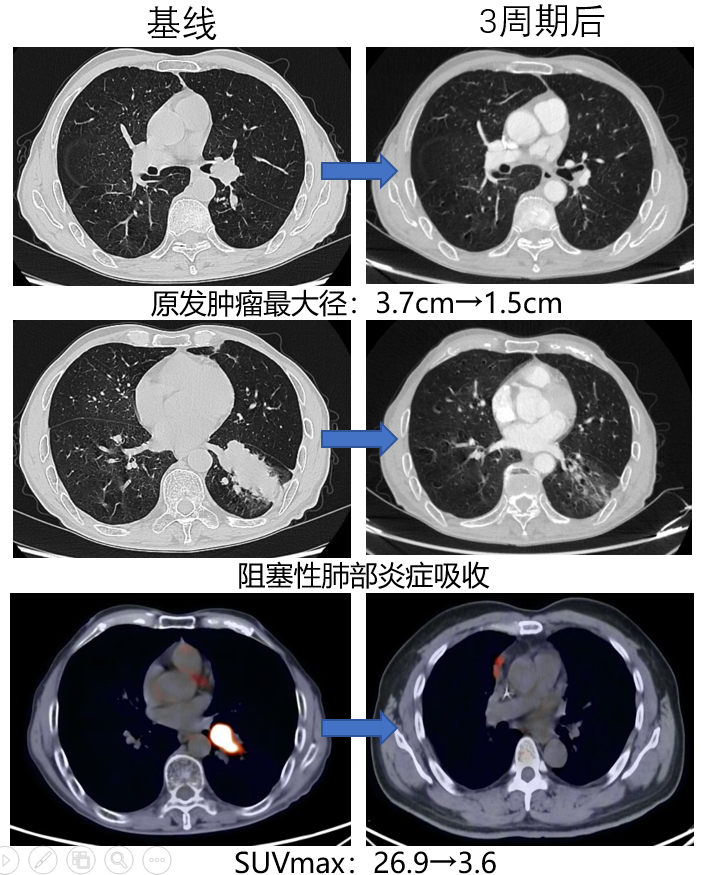

影像学与病理诊断

外院胸部CT平扫+增强:左肺中央型肺癌,合并远端阻塞性肺炎,左肺门见肿大淋巴结。

胸部CT增强:左肺中央型肺癌,伴远端阻塞性肺炎;左肺门见肿大淋巴结。病灶大小约3.7×2.3×3.3cm。

1.pngPET-CT:左下肺叶MT伴阻塞性肺部炎症,SUVmax 26.9;左肺门淋巴结转移,最小径0.7cm,SUVmax 11.3。

支气管镜:左下叶支气管开口完全阻塞。

活检病理:鳞状细胞癌。

分子检测:驱动基因(EGFR/ALK等)野生型;PD-L1 TPS 15%。

左下肺鳞癌伴肺门淋巴结转移(cT2aN1M0 IIB期)。PS:0-1分。